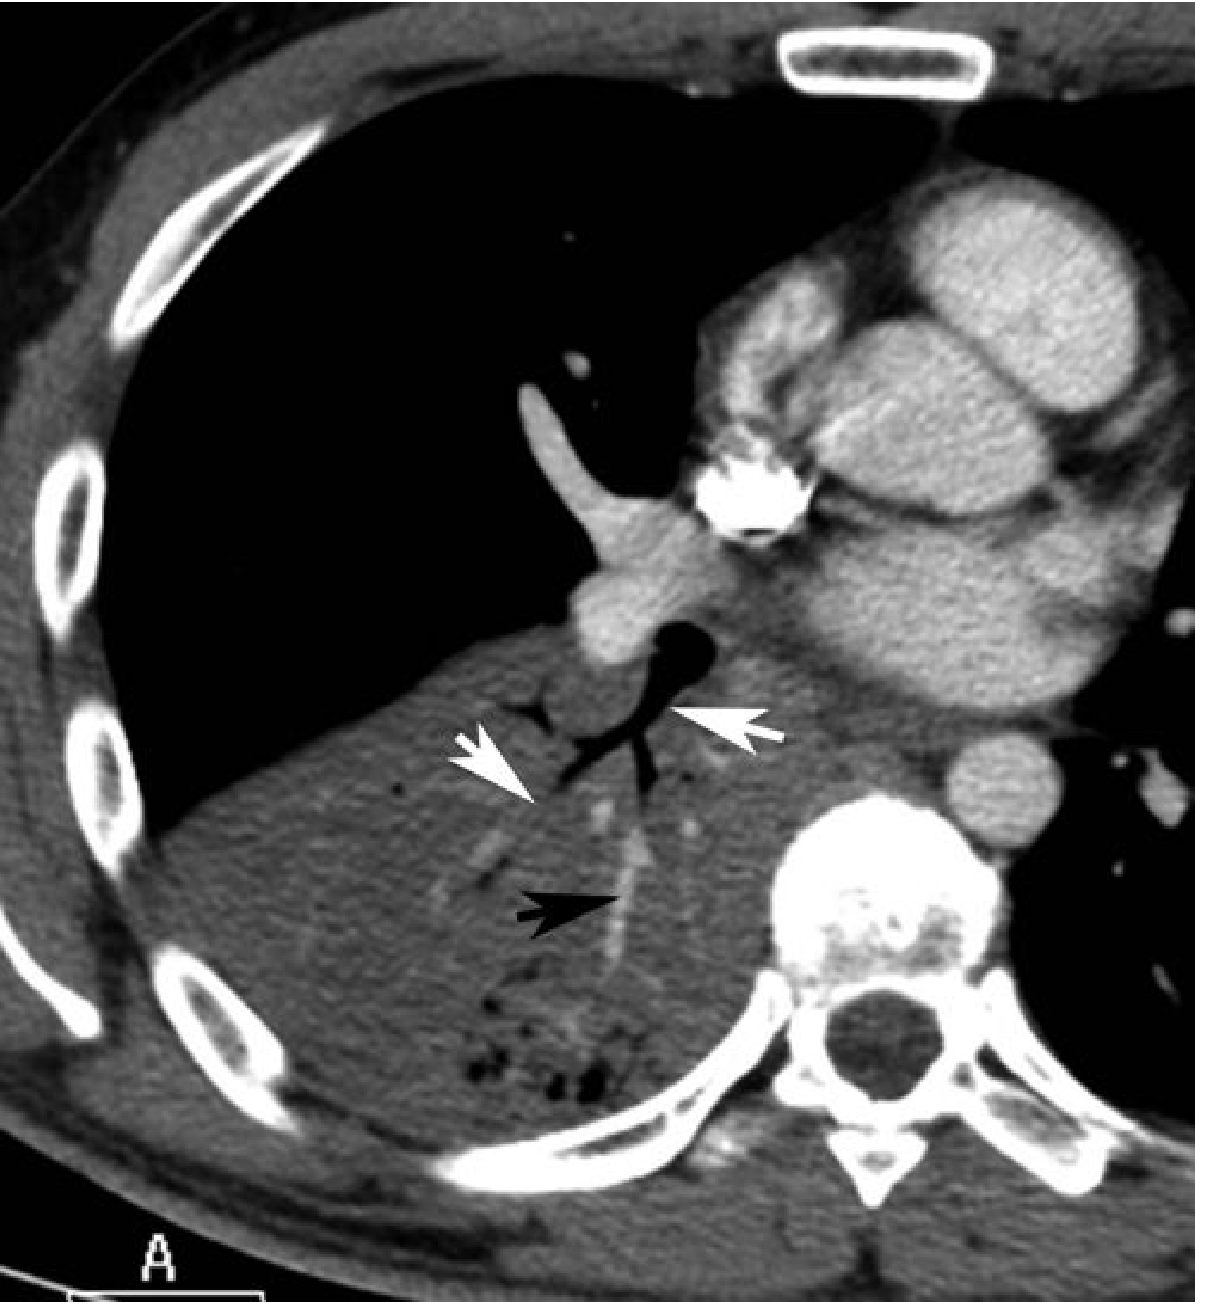

CT scan — lobar pneumococcal pneumonia with air bronchograms

Fig. 5.7 — CT of lobar pneumococcal pneumonia. Dense consolidation with air bronchogram (white arrows) and CT angiogram sign (black arrow). — Grainger & Allison's Diagnostic Radiology